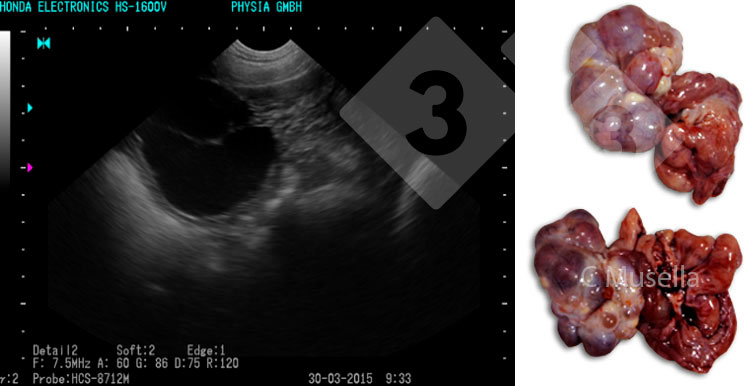

Le diagnostic de kystes ovariens uniques ou multiples est relativement simple, bien que l'identification complète du type de kyste par échographie ne soit pas toujours certaine.

Figure 3. Ovaires polykystiques.